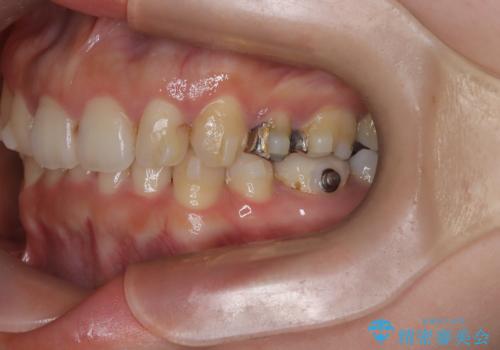

- 上下の歯の中心(正中)のズレと、口元の見た目を気にされて来院されました。精密な検査の結果、咬み合わせのバランスを整えながら、正中線を一致させる治療が必要と判断。患者様のご希望に合わせ、透明で目立ちにくいインビザライン(マウスピース矯正)による治療計画を立案しました。歯列全体を奥(遠心)へ移動させるためにゴムかけを併用。さらに、見た目を改善するため、既存の金属の被せ物をセラミッククラウンに交換することも治療計画に組み込みました。

今回の矯正治療では、透明なマウスピース型の装置インビザラインを使用しました。歯列を奥へ動かす遠心移動の効率を高めるため、患者様ご自身にゴムかけも行っていただきました。この併用によって、歯をより正確かつスムーズに動かすことができ、上下の歯の中心である正中線を一致させることが可能になりました。また、治療の最終段階では、以前から入っていた金属の被せ物を、天然歯に近い色合いのセラミッククラウンに交換。矯正治療と審美治療を組み合わせることで、機能的な咬み合わせの改善に加え、金属が見えない、より自然で美しい口元を獲得していただけました。